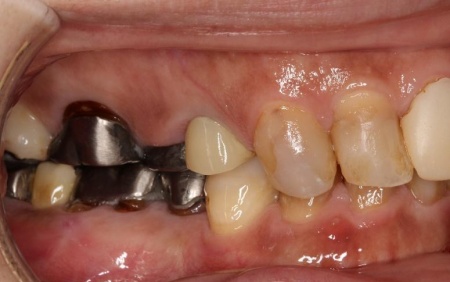

治療前

拝見したところ、もともと左上の歯と左下前歯が欠損しているうえ、奥歯の欠損も進んでいたため、噛み合わせが低くなっていました。

奥歯が噛み合わない状態になったことで、上前歯が前方に押し出され、出っ歯のようになっています。

また、下の歯は歯根だけが残る「残根」もあり、全体的に噛み合わせが不安定です。

さらに食いしばりの習慣があることから、残っている歯や顎関節に過度な負荷がかかっていると考えられます。

このまま放置すると、食いしばりによる歯の破折や欠損の増加、顎関節への負担増大、前歯の突出の進行などのリスクがあるため、早急に治療を開始する必要があると診断しました。